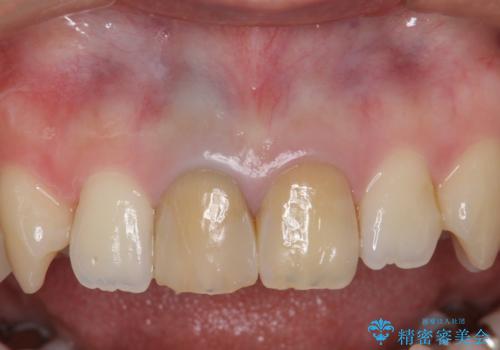

銀歯を白く セラミックインレーに

セラミックインレーにしています。